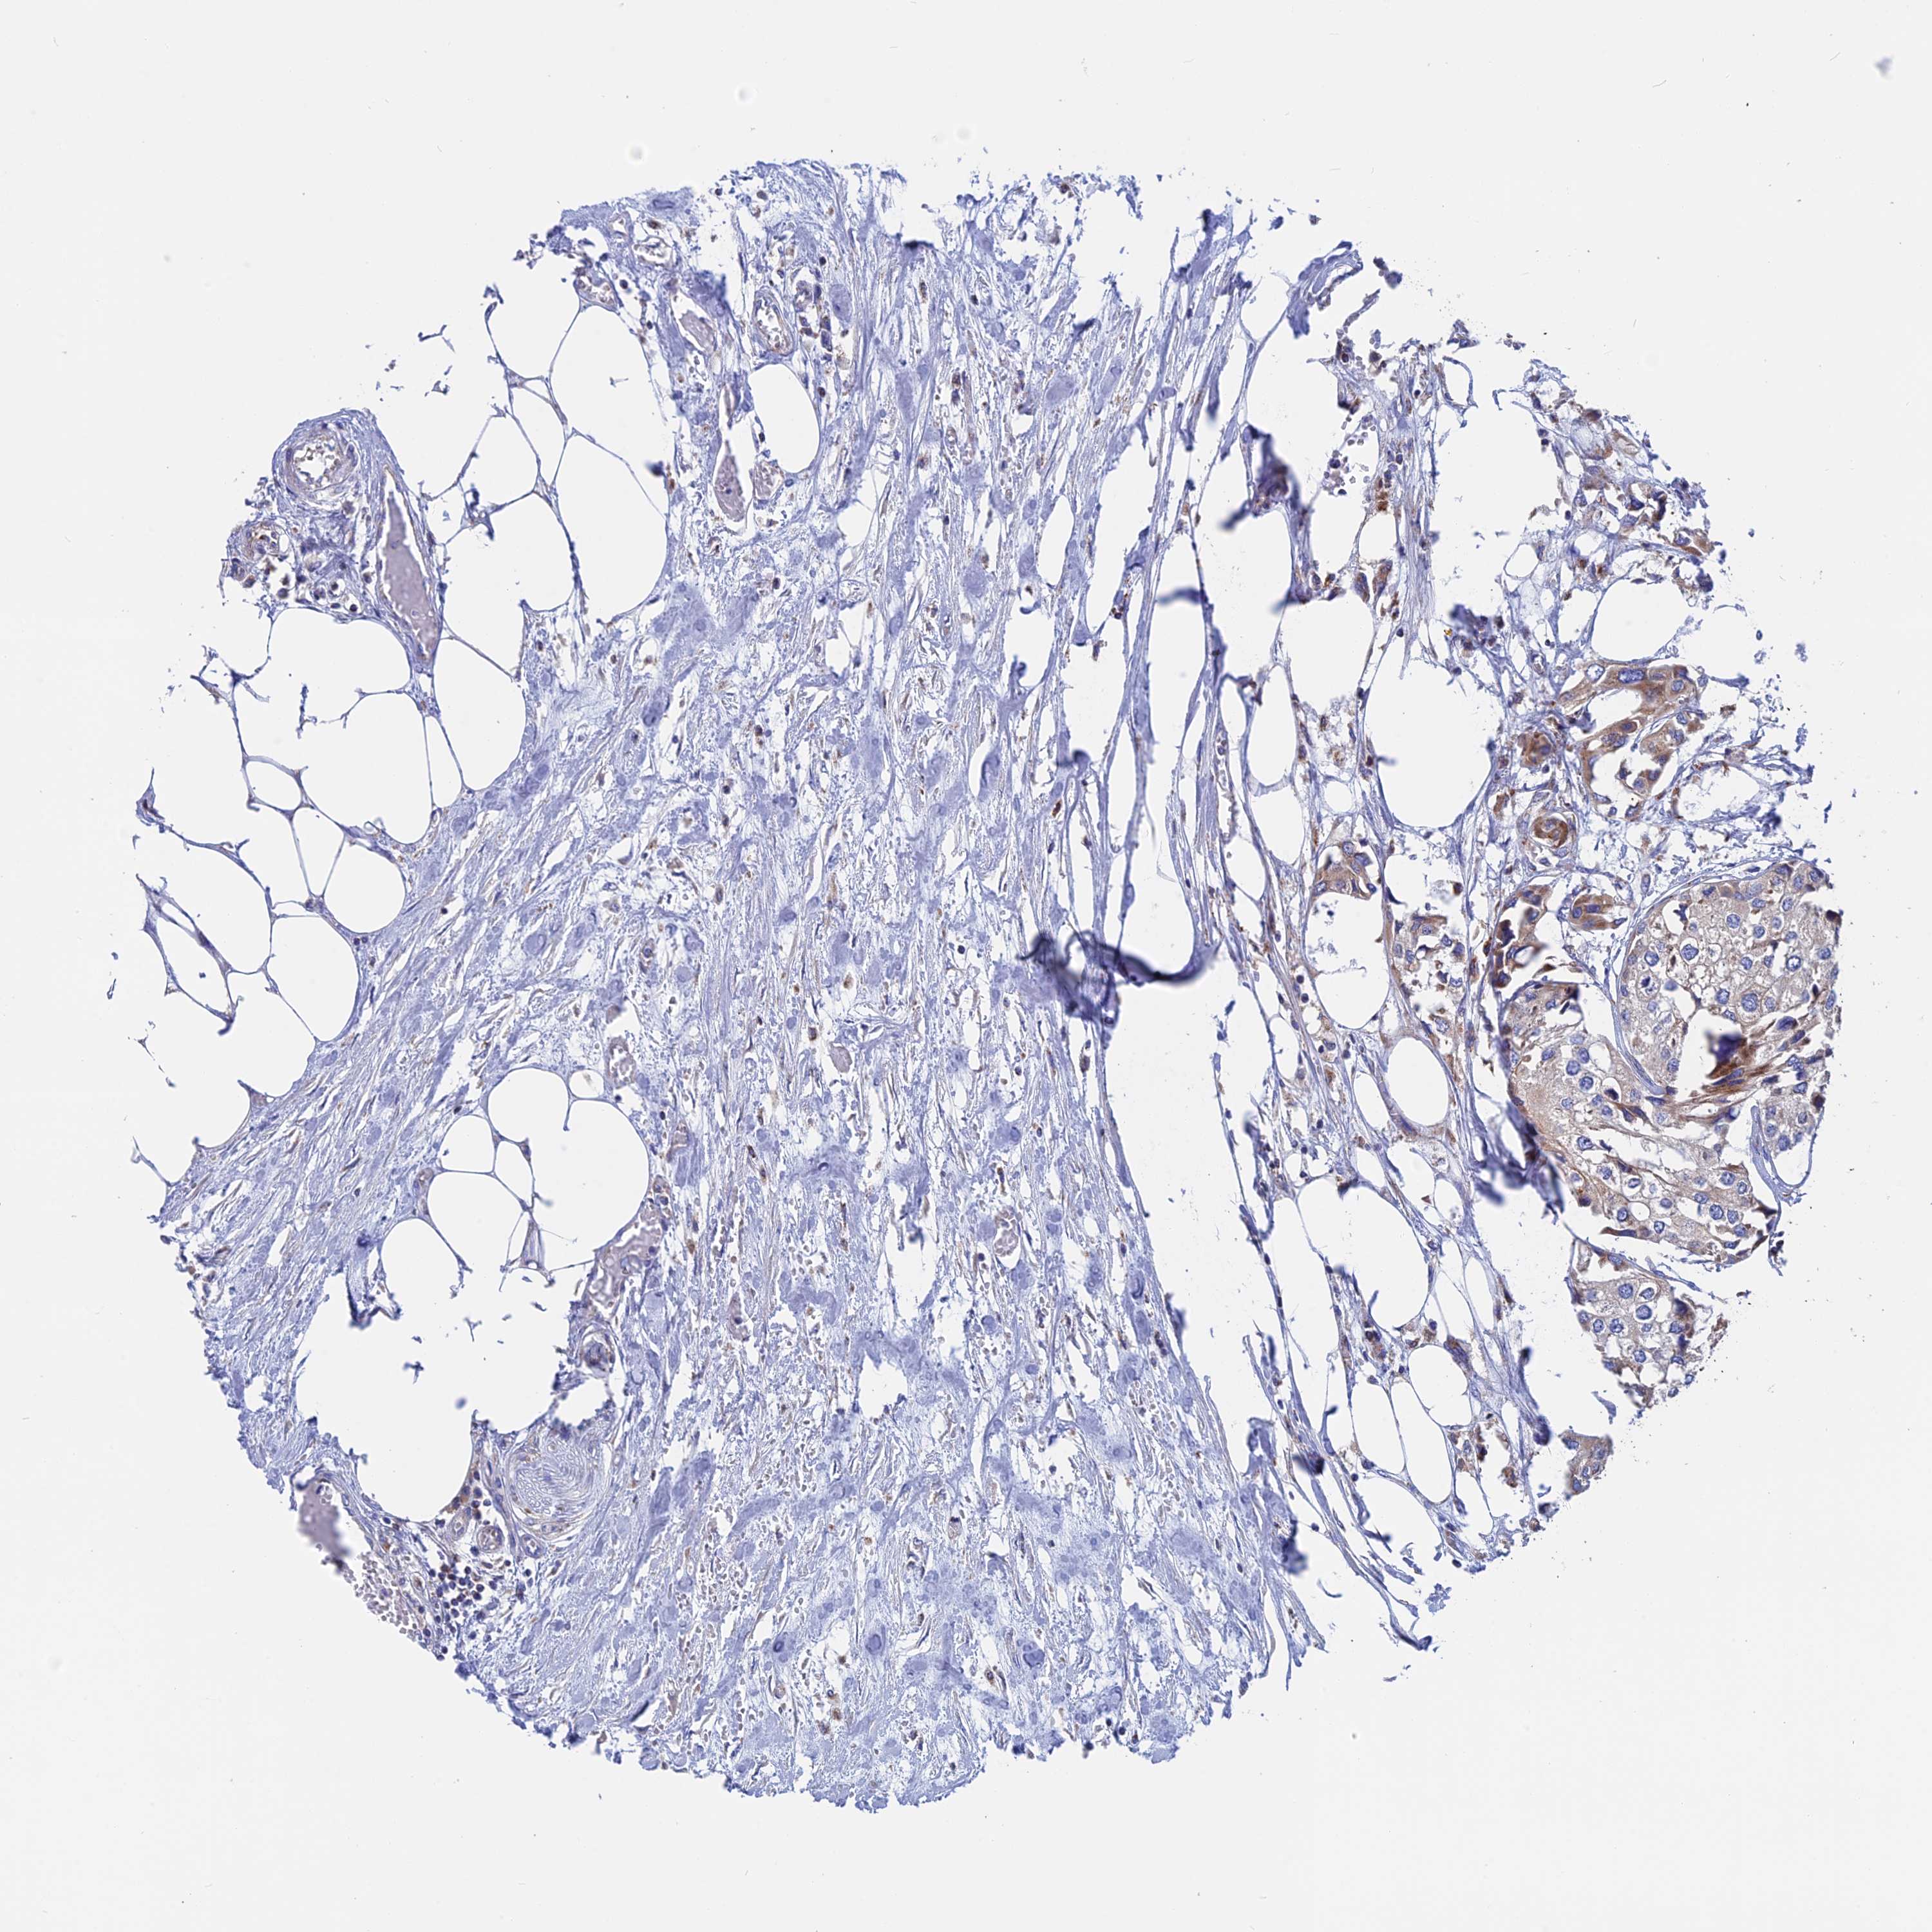

UROTHELIAL CANCER - Protein expressioni

A mouse-over function shows sample information and annotation data. Click on an image to view it in a full screen mode. Samples can be filtered based on level of antibody staining by selecting one or several of the following categories: high, medium, low and not detected. The assay and annotation is described here.

Antibody stainingi

Antibody staining in the annotated cell types in the current human tissue is reported as not detected, low, medium, or high, based on conventional immunohistochemistry profiling in selected tissues. This score is based on the combination of the staining intensity and fraction of stained cells.

Each image is clickable and will lead to virtual microscopy that enables deeper exploration of all samples and also displays staining intensity scores, fraction scores and subcellular localization as well as patient and tissue information for each sample.

Antibody HPA042629

Antibody HPA042838

Urothelial carcinoma, High grade

Urothelial carcinoma, Low grade